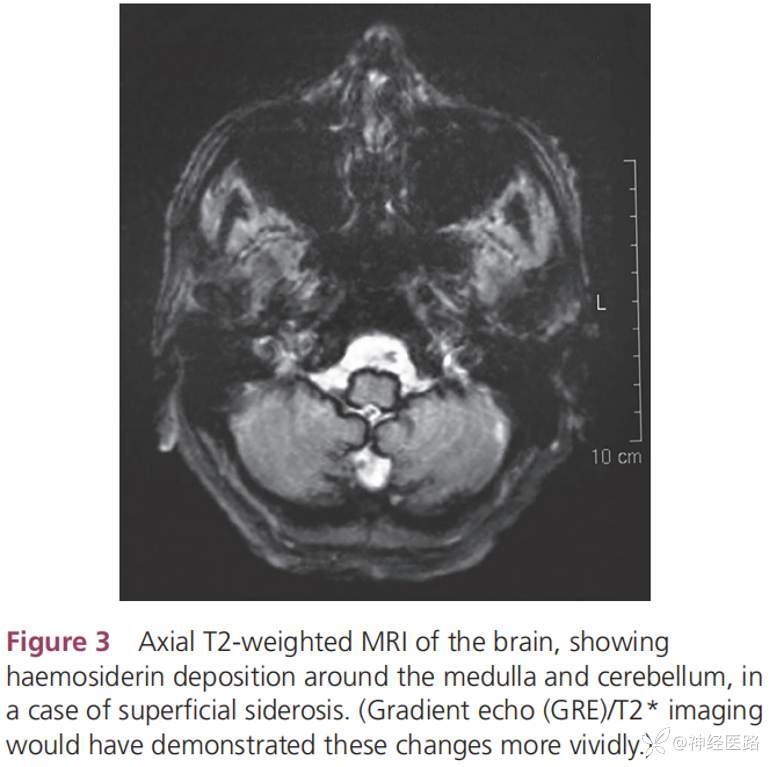

7.中枢神经系统表面铁沉积症(SSCNS):其中的经典型幕下型表面铁沉积症表现慢性共济失调、听力下降、锥体束征临床三联征,但只有39%的患者表现为上述三联征。其他临床表现包括认知障碍、膀胱功能障碍、嗅觉障碍、瞳孔不等大、感觉体征,少见表现包括颈痛、背痛、吞咽困难、双侧坐骨神经痛及下运动神经元体征等。